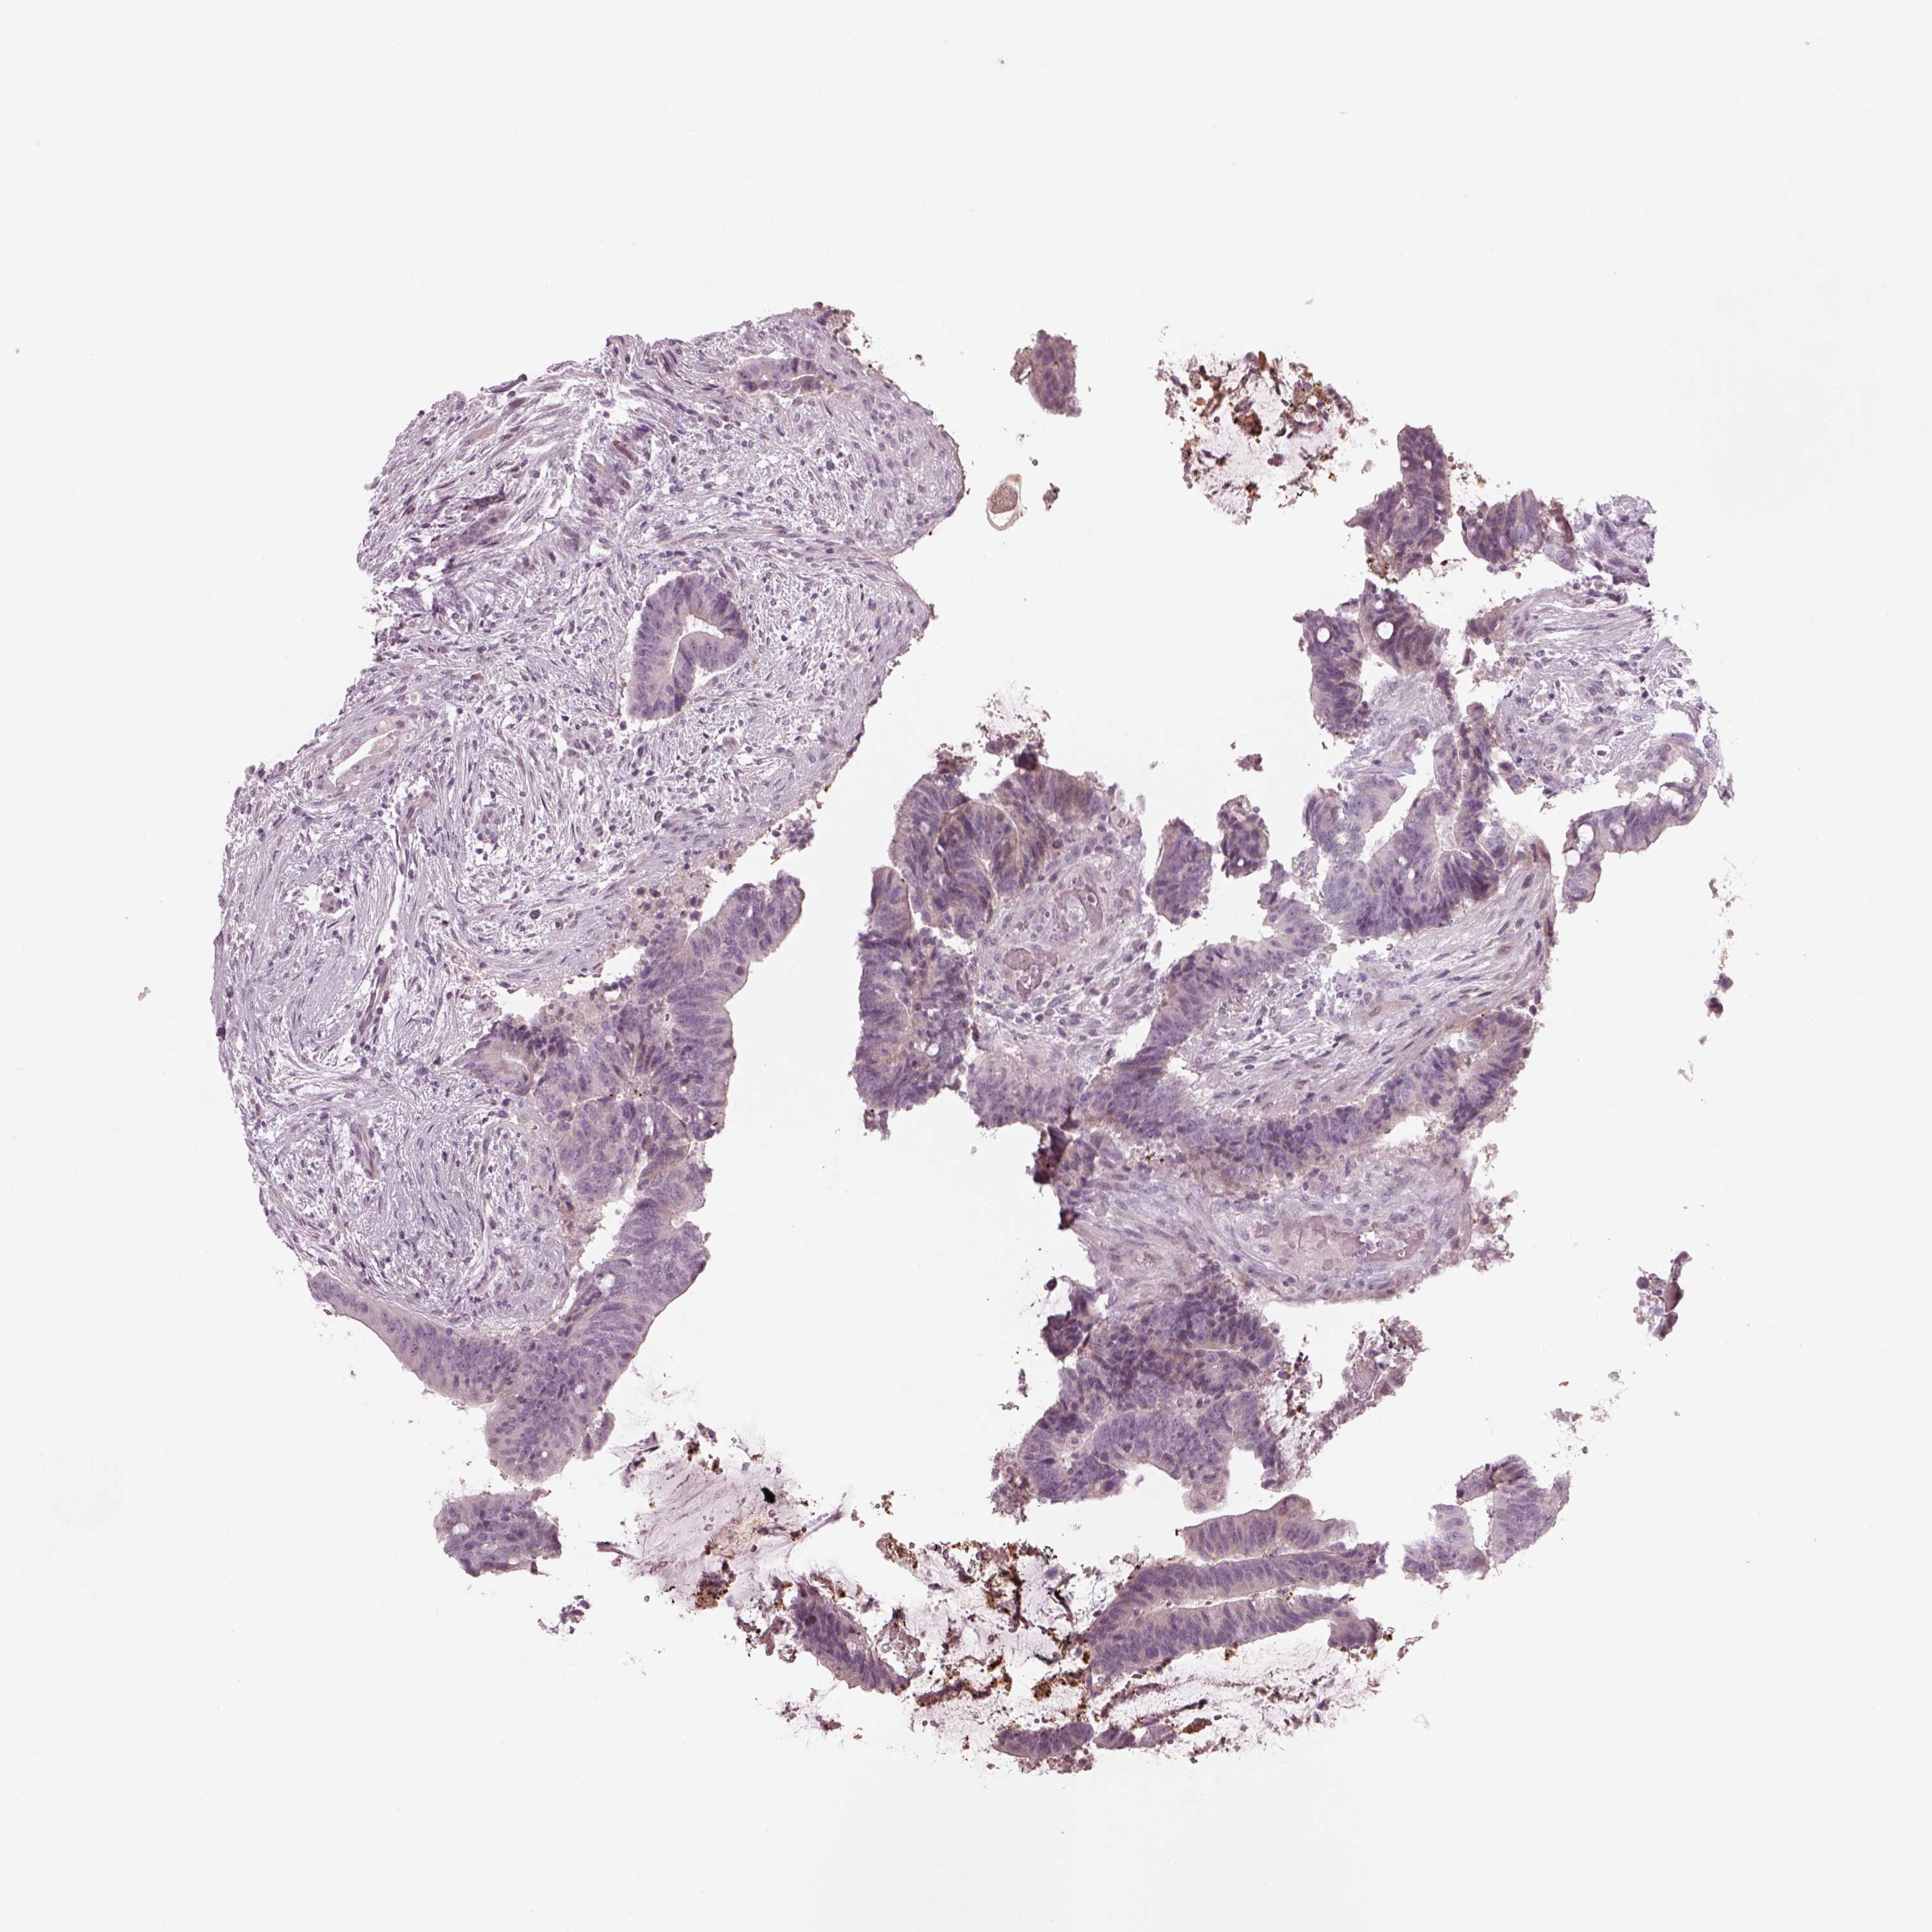

CANCER COLORECTAL CANCER Show tissue menu

Colorectal cancer

Human cancer

Colon adenocarcinoma